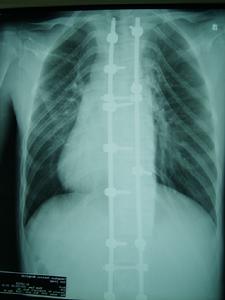

3、心血管系統:約80%的患者伴有先天性心血管畸形。常見主動脈進行性擴張、主動脈瓣關閉不全,由於主動脈中層囊樣壞死而引起的主動脈竇瘤、夾層動脈瘤及破裂。 二尖瓣脫垂、二尖瓣關閉不全亦屬本徵重要表現。可合併先天性房間隔缺損、室間隔缺損、法樂氏四聯征、動脈導管未閉、主動脈縮窄等。也可合併各種心律失常如傳導阻滯、預激綜合徵、房顫、房撲等。

馬凡氏綜合症 • 雞胸;

• 漏斗胸,需外科矯治;

• 脊柱側彎大於20度,或脊柱前移(側彎計);